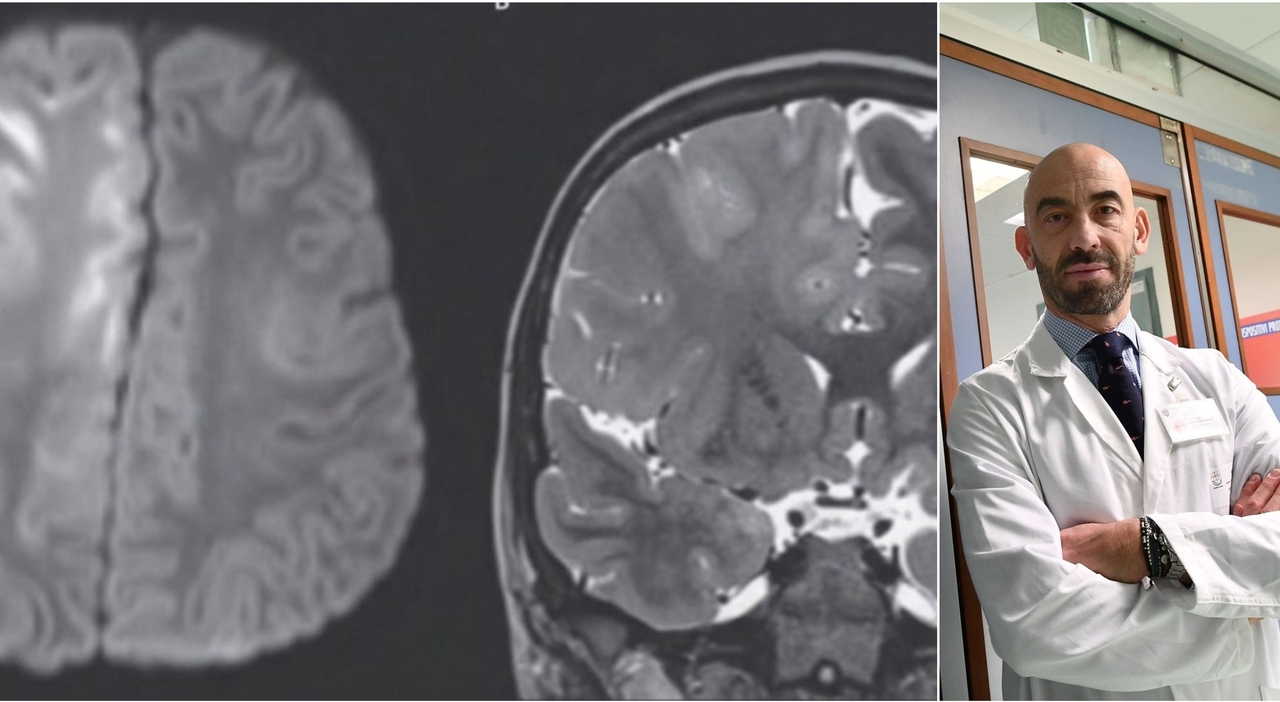

«Ecco cosa ha fatto il #Morbillo al cervello di un bambino che lo ha avuto a 7 mesi». L'allarme di Bassetti